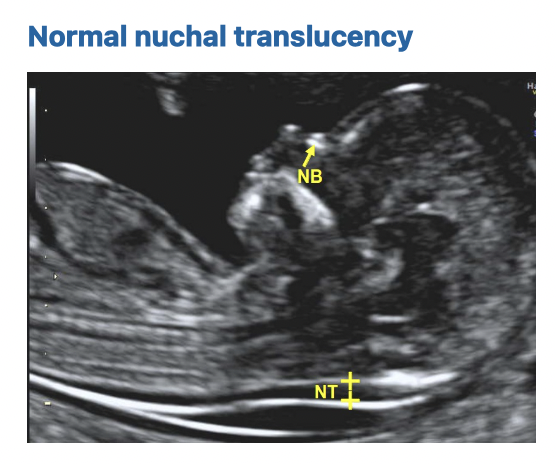

1. Nuchal Translucency Ultrasound

Conducted between 11 weeks 2 days and 13 weeks 6 days of pregnancy, this ultrasound measures the thickness of the nuchal translucency—a fluid layer behind the baby’s head and neck. Abnormal thickness may suggest chromosomal abnormalities. The ultrasound also examines other fetal structures for a comprehensive assessment.